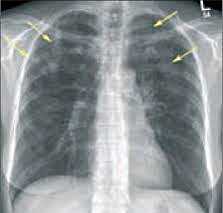

1. Рентгенологическая картина эозинофильных заболеваний:

• ПЛЭ:

о Субсегментарные затемнения:

- Периферические, одно- или двухсторонние, преходящие или мигрирующие, обычно разрешающиеся в течение одного месяца

• ХЭП:

о Двухсторонние несегментарные симметричные участки консолидации с преимущественной локализацией в наружных отделах и верхних долях легких: «фотографический негатив отека легких»